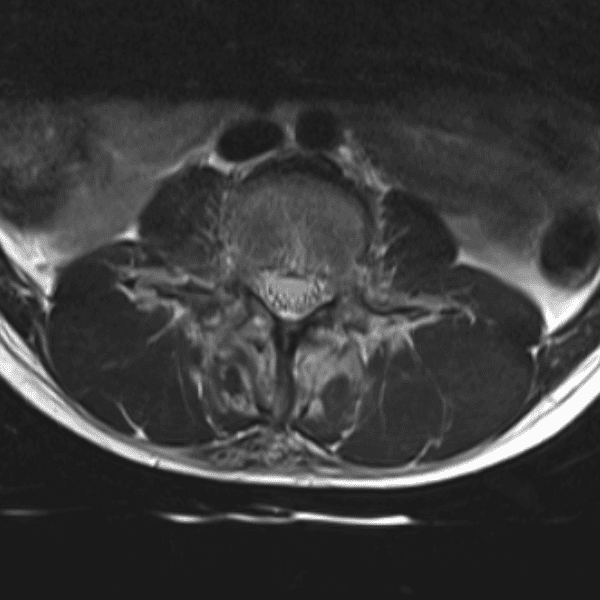

Simulates call by including subtle or difficult cases and some normals.

35 cases